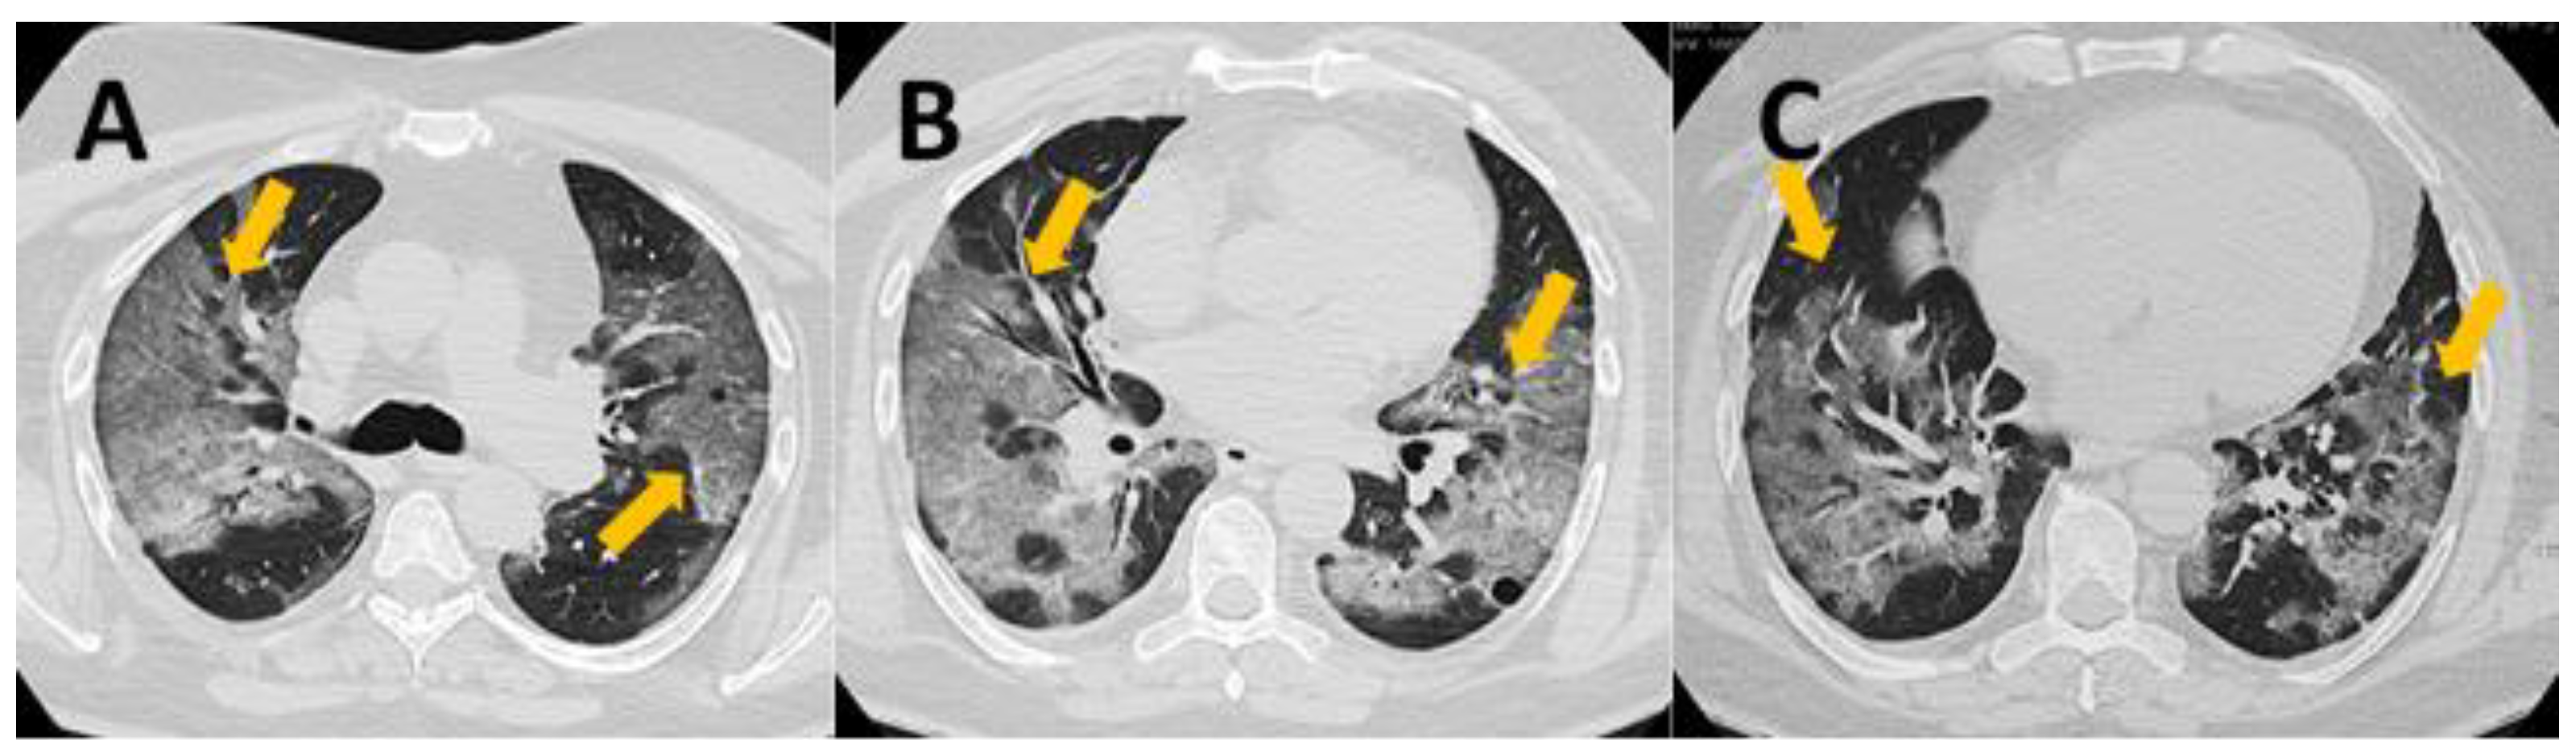

2.2. CT Severity Score

- 0 points—normal lung

- 1–5 points—mild changes

- 6–10 points—moderate changes

- 11–15 points—severe changes

- 16–25 points—critical changes